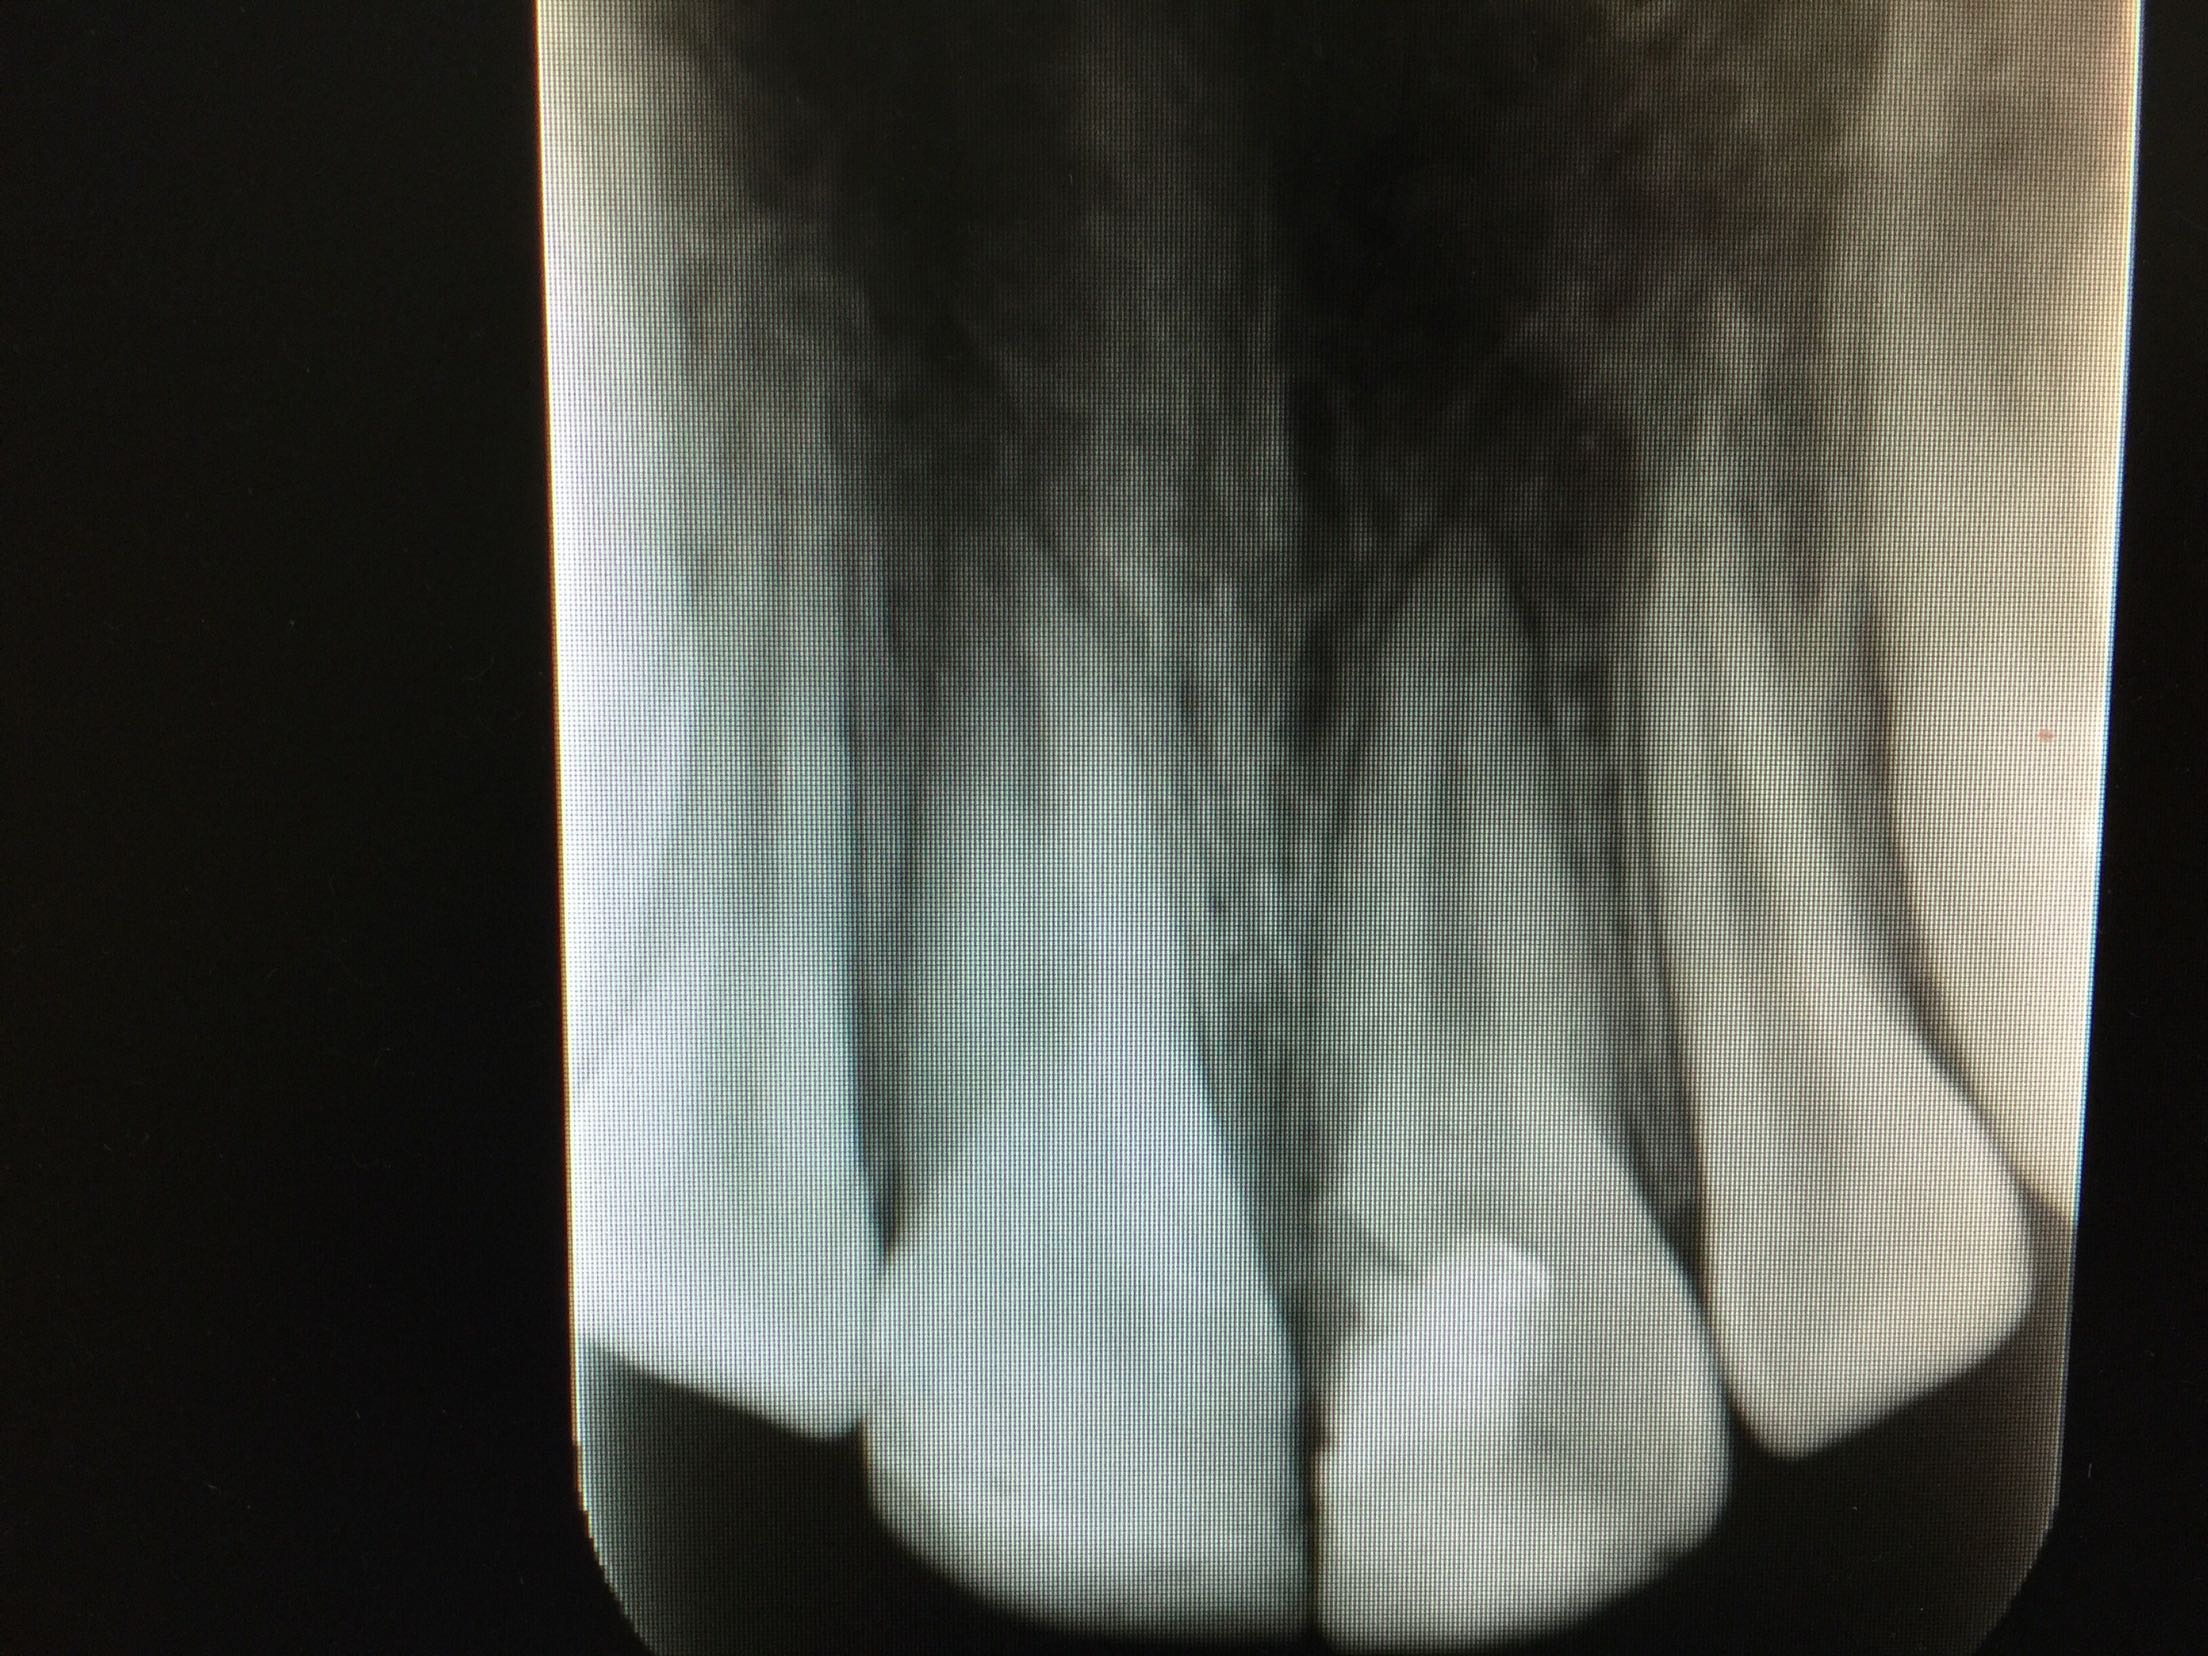

复诊,11,21牙进口玻璃离子垫底,前牙美容修复术调合,抛光。 3周后复诊:牙髓电活力测试11牙14,21牙15。 拍片:

11,21牙牙周膜腔未见明显增宽,很尖周无暗影。 建议继续拍片观察。 一月后复诊:牙髓电活力测试11牙13,21牙15。 拍片:11,21牙牙周膜腔未见明显增宽,很尖周无暗影。 建议11,21前牙树脂功能修复。 处置:行11牙,21牙牙树脂修复术。继续观察,约复诊。